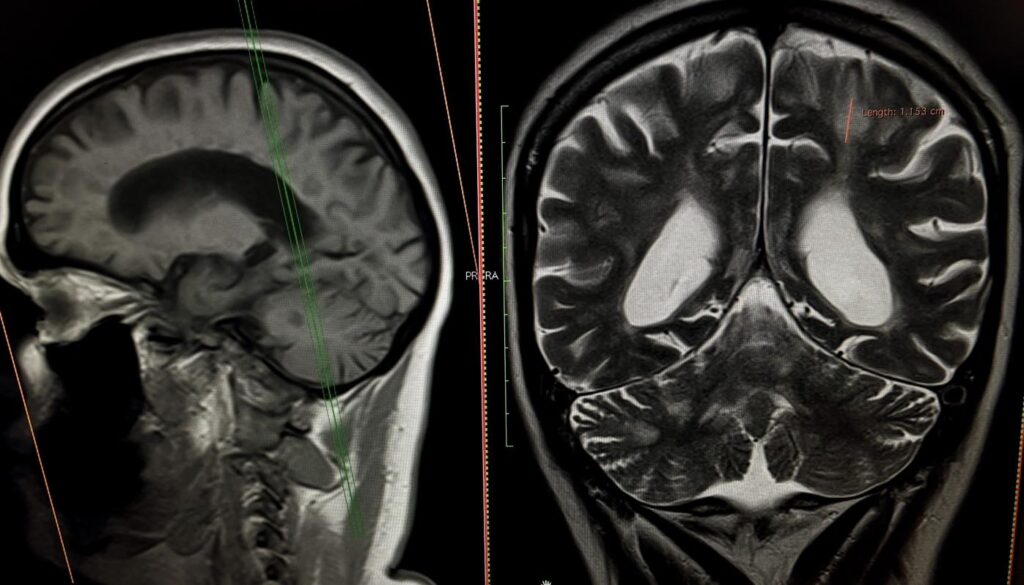

40-річна Соломія не могла самостійно дихати, їсти, розмовляти та ходити. Саме у такому стані вона потрапила у приймальне відділення Університетської лікарні. З 2018 року Соломія страждає на розсіяний склероз, але жодного разу не лікувала це захворювання. Коли вона вже була без свідомості, мама викликала “швидку”

Замість Соломії дихав апарат ШВЛ, замість повноцінної їжі вона отримувала спеціальне харчування через назогастральний зонд. Крім неврологічних проблем, у пацієнтки діагностували важке токсичне ураження печінки, тромбоемболію легеневих артерій, тромбофлебіт (запалення стінок вен і формування тромбу у судині) у нозі і запалення вуха.

За 20 днів лікування у Клініці неврології та нейрохірургії Університетської лікарні Соломія буквально ожила – повернулася до свідомості, знову може ковтати і їсти, розмовляє, самостійно дихає і вже робить перші кроки.